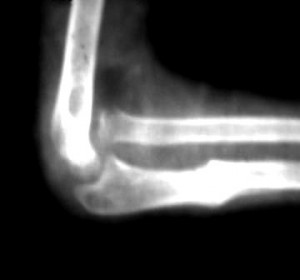

La radiografía es una técnica utiliza para el diagnóstico de fisuras, grietas, poros,…

Su uso se centra en medicina (como por ejemplo fracturas de huesos) como en usos industriales (búsqueda de defectos de construcción o desgaste, como grietas).